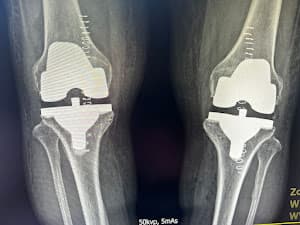

Desember 2022 Saya punya pengalaman sendiri melahirkan putri saya dengan Dr. Norliza.. MasyaAllah beliau sangat baik, sopan, dan sabar.. insya Allah lain kali kami akan terbang kembali dari Arab Saudi ke Batu Pahat hanya untuk pelayanannya.. insya Allah.. terima kasih Dokter atas pengertian dan pelayanan Anda yang luar biasa. Juli 2023 adik bungsu saya juga menjalani operasi, tidak ingat nama dokternya. Tapi hasilnya juga sangat baik. Dokter bahkan menjelaskan mengapa dan bagaimana beliau membantu dalam kasusnya, dan beliau juga menindaklanjuti sendiri menanyakan kondisi adik saya setelah operasi.. Alhamdulillah beliau sudah pulih. Maret 2024.. ibu saya menjalani operasi besar penggantian lutut total. Oleh Dr. Ezat.. Masya Allah Dr. Ezat ini sungguh luar biasa. Beliau melayani ibu saya seperti anaknya sendiri dan stafnya juga, jika mengadu ada masalah pada ibu saya, mereka seperti saudara kandung. Masya Allah. Hasil operasinya sangat luar biasa.. alhamdulillah.. masalah lutut ibu saya sudah stadium 4-5. Memang sudah tidak bisa digunakan. Jadi alhamdulillah beliau sedang pulih dan yang terbaik adalah operasinya alhamdulillah ternyata tidak sesakit yang kami dengar dan bayangkan. Setelah satu bulan lebih ibu saya bisa berjalan tanpa alat bantu. Sangat senang dan bersyukur dengan hasilnya. Alhamdulillah. Saya sangat menyarankan siapa pun yang punya masalah tulang, lutut untuk menemui Dr. Ezat ini. Anda tidak akan kecewa dengan pelayanannya.. Insya Allah nanti saya akan membagikan pengalaman ibu saya di FB. Terima kasih atas pelayanan Anda yang luar biasa Dr. Ezat. Selamat KPJ BP, Anda punya spesialis yang sangat baik!